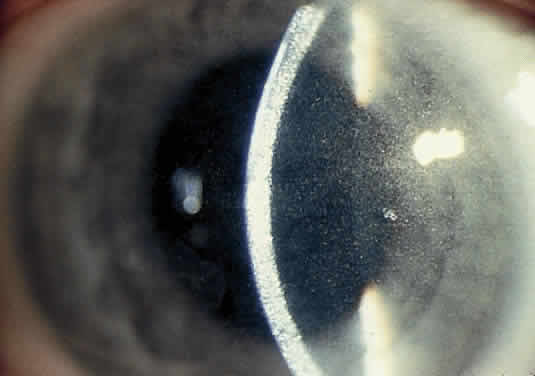

OCULAR FINDINGS. One of the few truly diagnostic and pathognomonic physical signs in clinical medicine is a Kayser-Fleischer corneal pigment ring found in patients with Wilson's disease (Fig. 5).This ring is recognized as a golden-brown, ruby-red, or green band of 1.0 to 3.0 mm, starting at the limbus but at the level of Descemet's membrane.53 The color of the ring is presumably caused by scattering and reflection of incident light and by photointerference effects created by the layers of copper granules. Such variables as size, shape, and unit density of the granules may account for the different appearances of the Kayser-Fleischer ring. The course of the Kayser-Fleischer ring has been well documented.54,55 The site of earliest pigment deposition is an arc in the superior periphery of the cornea from the 10- to 2-o'clock meridian. The arc spreads slowly toward the horizontal plane and gradually broadens. Later in the progression of the ring formation, a band appears inferiorly as a crescent stretching from the 5- to 7-o'clock positions. In time, the two arcs meet. With treatment, the sequence of events is reversed, and after the copper has reabsorbed, a pitted or beaten silver pattern may become apparent at the previous site of the ring. This is an indication that treatment has produced a negative copper balance.49 Decreased visual acuity is not a problem. Rarely, copper is deposited in the crystalline lens, giving an anterior subcapsular “sunflower” cataract.

Fig. 5. Wilson's disease. Kayser-Fleischer peripheral corneal ring. Copper pigment at level of Descemet's membrane.

PATHOLOGY. Electron microscopic, x-ray energy spectroscopic, and atomic absorption spectroscopic studies of the Kayser-Fleischer rings have revealed electron-dense granules rich in copper and sulfur in both the peripheral and the central region of the cornea, but more abundantly at the periphery. The association of copper with sulfur suggests that a sulfur-containing moiety functions in binding copper.59